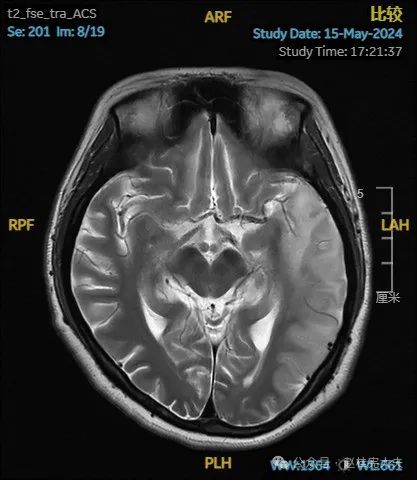

入院后给予精氨酸,左卡尼丁,辅酶Q10,维生素E等治疗。患者病情稳定好转中,2天后意识清楚,语言表达仍欠佳。当天复查颅脑磁共振如下:

以上为患者发病后3次的颅脑磁共振片子,临床诊断基本上可以确认了,希望患者逐渐恢复!